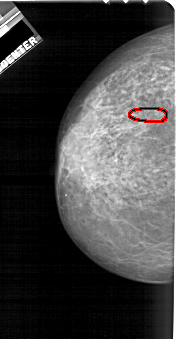

A_1722_1.LEFT_MLO

LEFT_MLO LINES 5491 PIXELS_PER_LINE 3091 BITS_PER_PIXEL 12 RESOLUTION 43.5 OVERLAY

FILE: A_1722_1.LEFT_MLO.OVERLAY

TOTAL_ABNORMALITIES 1

ABNORMALITY 1

LESION_TYPE CALCIFICATION TYPE PLEOMORPHIC DISTRIBUTION SEGMENTAL

ASSESSMENT 4

SUBTLETY 2

PATHOLOGY MALIGNANT

TOTAL_OUTLINES 1

BOUNDARY